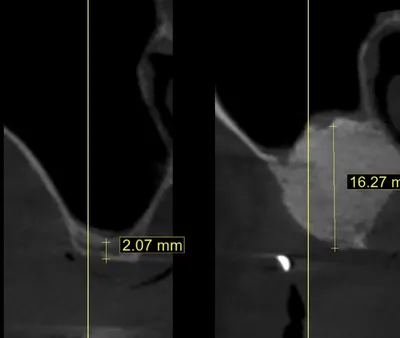

Greffe de sinus et sinus lift par spécialiste en implantologie Marseille

Découvrez tout sur le sinus lift et les greffes de sinus en implantologie dentaire : indications, techniques, bénéfices et résultats pour assurer la réussite de vos implants dentaires même en cas de manque osseux.

Le traitement des cas complexes en implantologie dentaire nécessite d'avoir recours à des techniques de greffes osseuses et de régénération osseuse guidée.